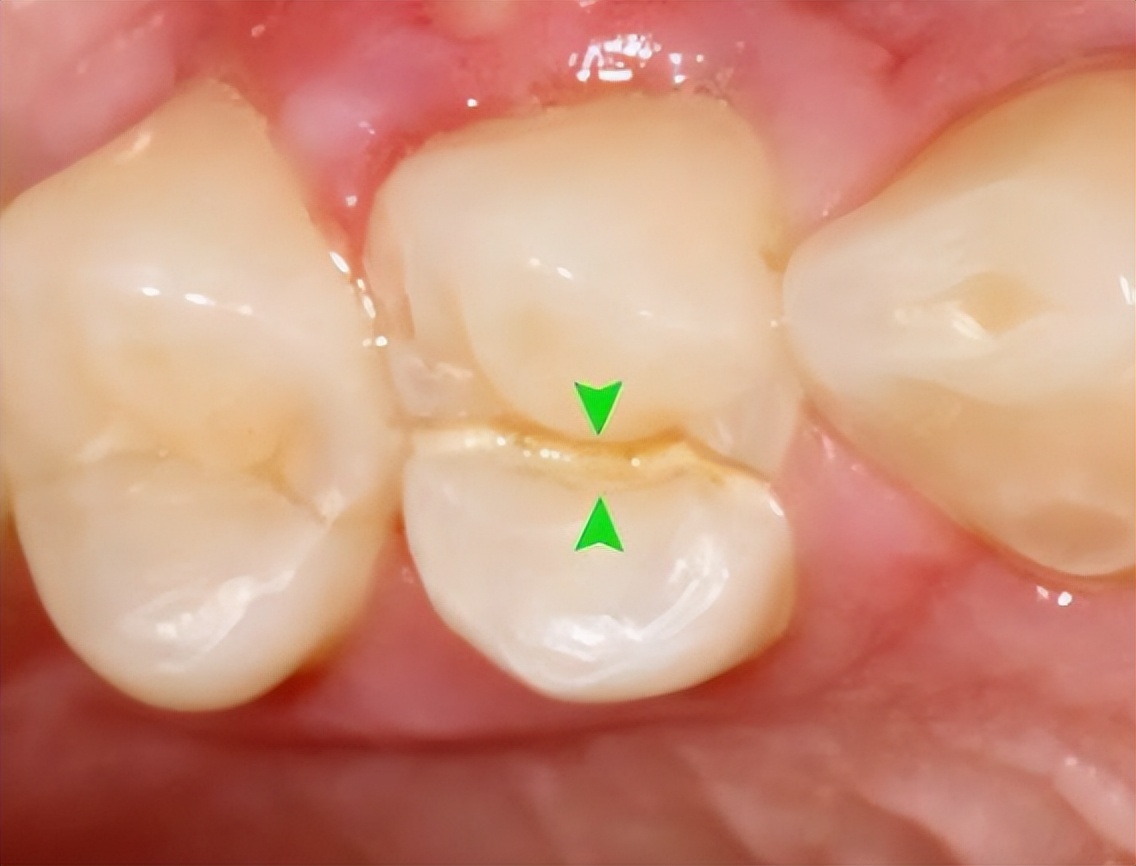

真实病例:下面这幅图片就是一个牙科医生发出来的一个患者的牙,之前做了“根管治疗”后,没有及时做“牙冠”。

结果导致吃东西时把原来做过‘根管治疗’的牙直接劈成了2半。这不是既麻烦又难受?后悔都来不及了!!